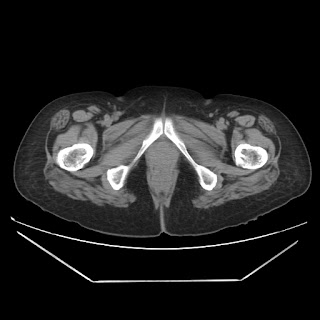

Her abdominal X-ray also reveals a right renal stone although she never complained of renal colic.

CT images: